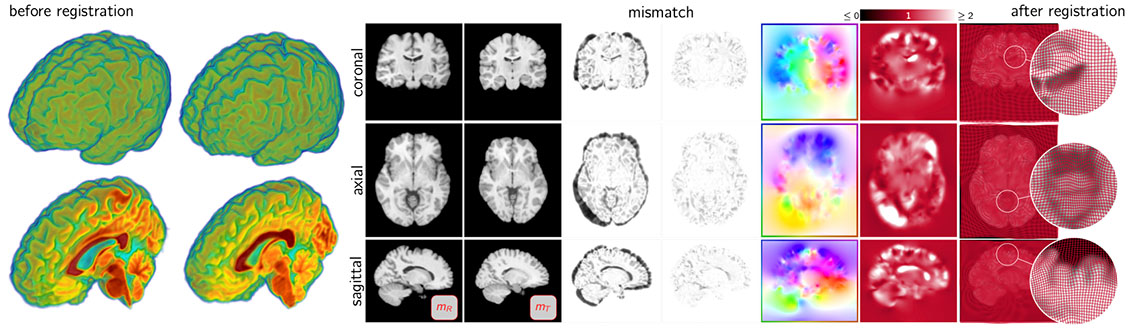

Mang and his lab will work on inverse problems. This is a particular class of problems in which scientists try to infer unknown causes based on observations of their effects. For example, one seeks to identify the best parameters of a mathematical model (i.e., a mathematical abstraction of a physical phenomenon, such as disease progression), so that the model output (a computer simulation) best matches some observed data.

The ultimate aspiration of his group’s research is to use computer simulations to aid decision-making or enable model-based predictions. To make these predictions useful in practice, his group wants to be able to quantify the level of confidence they have in the generated predictions.

For example, Mang and his lab want to be able to tell a clinician how uncertainties propagate through computed predictions of tumor growth. Computing these confidence estimates and developing approaches to reduce uncertainties adds significant mathematical and computational challenges, resulting in intractable run times if suboptimal algorithms are considered.

To address these issues, his group will not only develop the methods to make predictions on physical phenomena, such as tumor growth, but they will do it in an efficient way. They will use dedicated hardware, like graphics processing units, and supercomputing platforms, for problems that have a lot of unknowns/model parameters.

Potential applications of his work include patient-specific simulation of the progression of a disease, climate modeling, weather predictions, and hurricane or tsunami predictions.